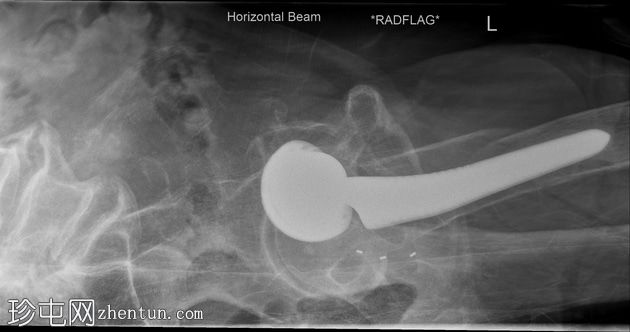

X光片

侧面

可见左髋关节假体。左侧股骨近端存在轻微移位的假体周围骨折。

初次X光片和后续CT扫描均可见左股骨假体周围骨折。温哥华分类系统是目前最广泛使用的髋关节假体周围骨折分类系统。本例患者为温哥华B2型骨折。